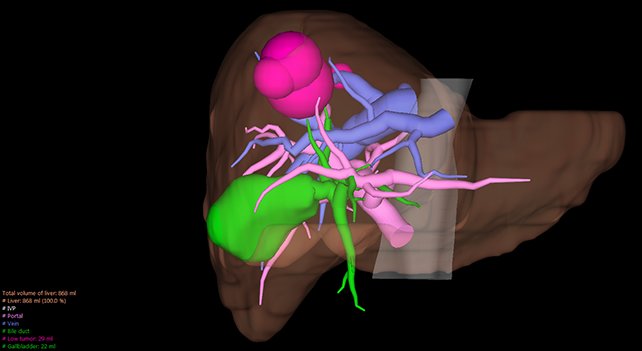

ANYTHINK 经导管主动脉瓣膜置换术分析系统